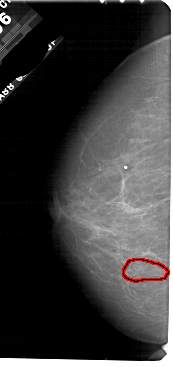

FILE: A_1839_1.LEFT_MLO.OVERLAY

TOTAL_ABNORMALITIES 1

ABNORMALITY 1

LESION_TYPE CALCIFICATION TYPE PLEOMORPHIC DISTRIBUTION CLUSTERED

ASSESSMENT 4

SUBTLETY 3

PATHOLOGY BENIGN

TOTAL_OUTLINES 1

BOUNDARY